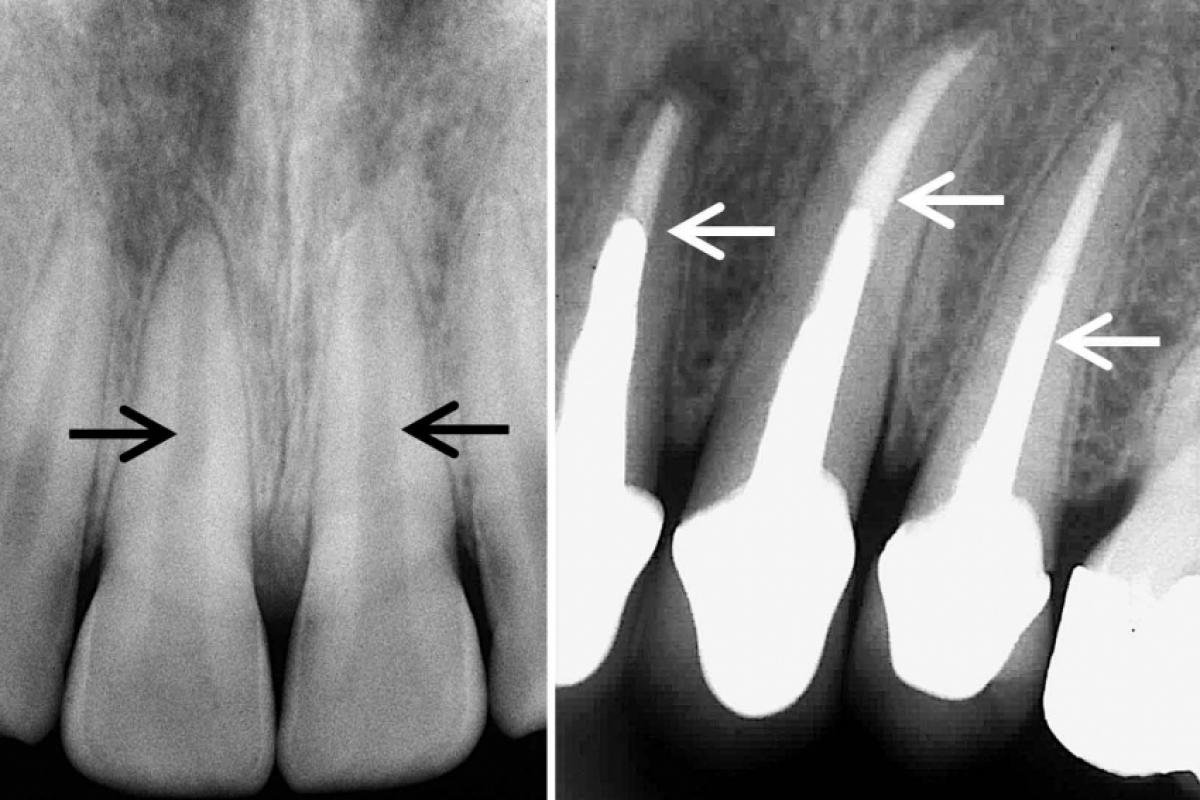

A raiz sumiu: dentes são reabsorvidos